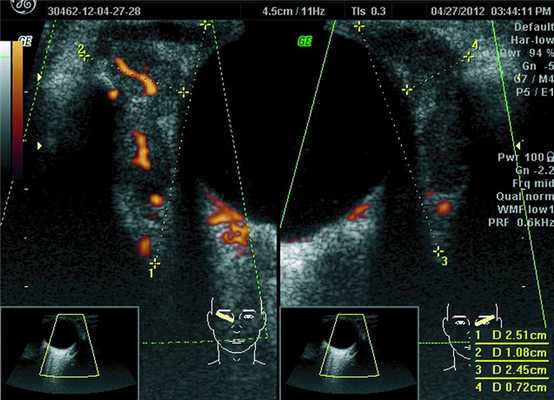

При ультразвуковом исследовании орбит 32 пациентов у 23 было выявлено увеличение линейных и объемных размеров слезных желез (рис. 1), Рисунок 1. Эхограмма глазного яблока и слезной железы в косой проекции с правой и левой стороны. На ультразвуковом срезе размеры слезных желез по глубине и ширине значительно увеличены (OD — 2,51 см на 1,08 см, OS — 2,45 см на 0,72 см). Видны извитые сосудистые цветовые карты. Внутри слезной железы визуализируются обширные сливные зоны разряжения. что сопровождалось изменениями функции органа и развитием синдрома сухого глаза в 8 случаях. Увеличение слезных желез в 19 случаях было парным, в 4 — односторонним.